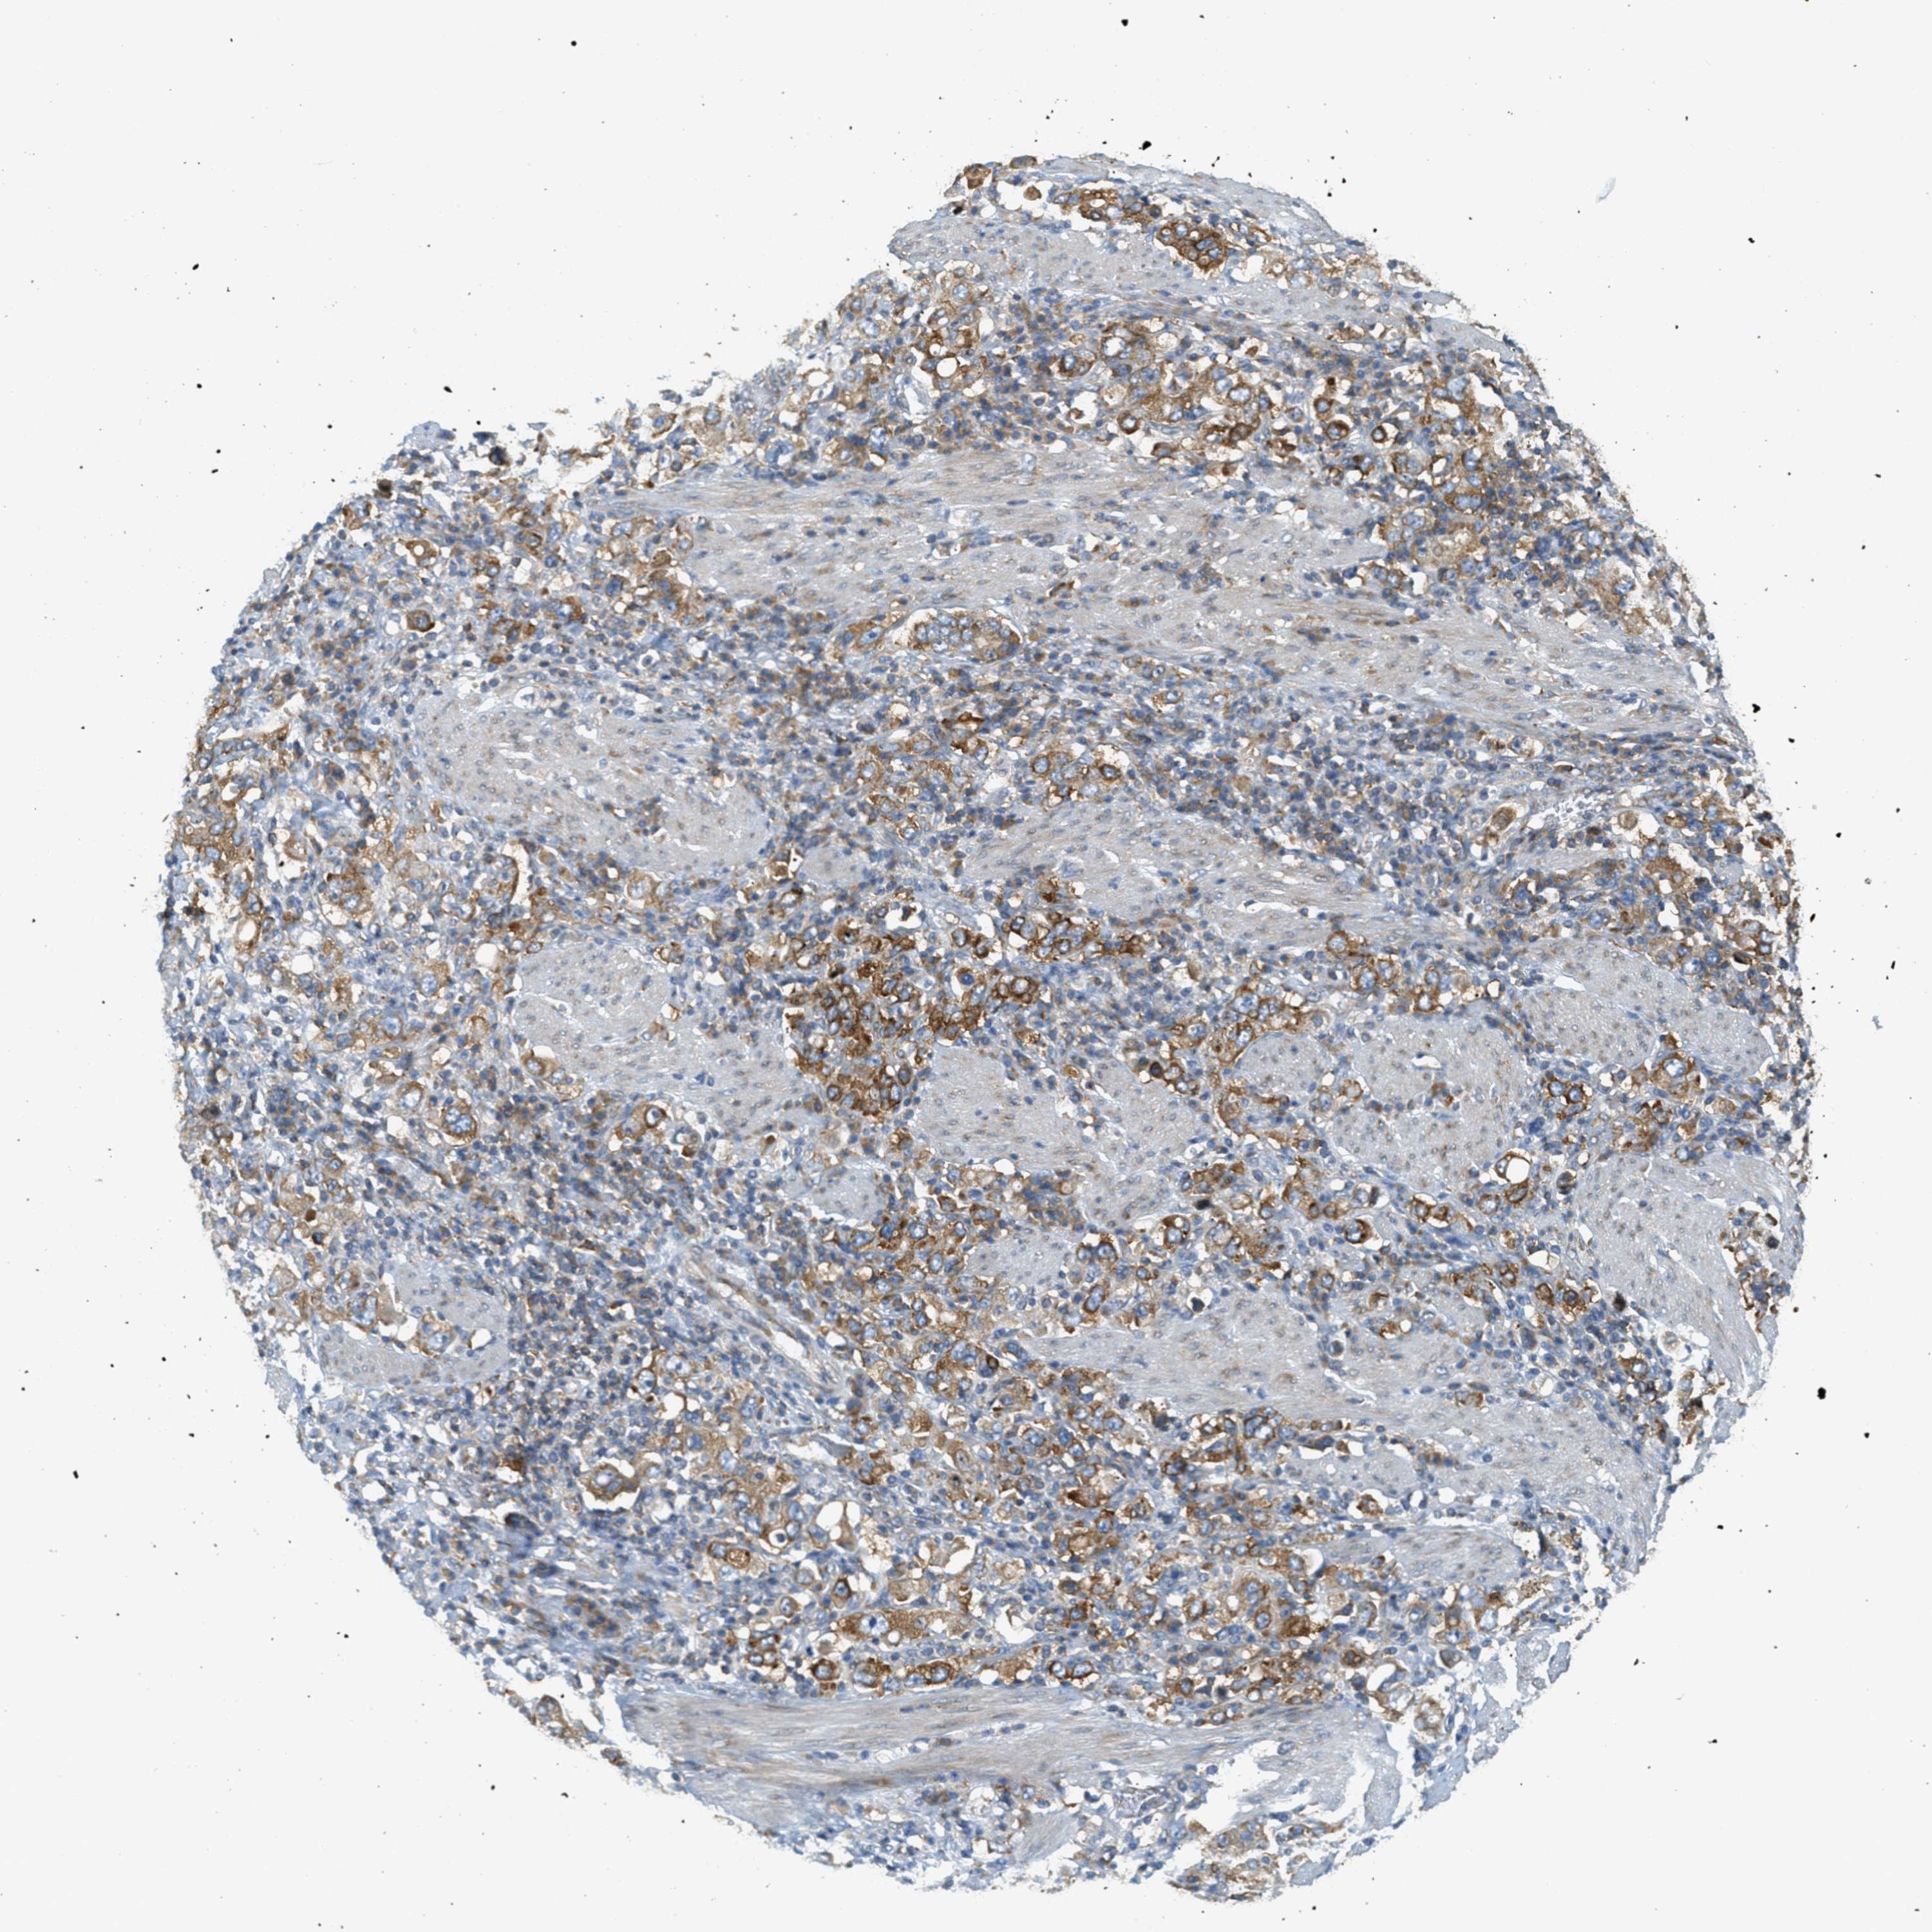

STOMACH CANCER - Protein expressioni

A mouse-over function shows sample information and annotation data. Click on an image to view it in a full screen mode. Samples can be filtered based on level of antibody staining by selecting one or several of the following categories: high, medium, low and not detected. The assay and annotation is described here.

Antibody stainingi

Antibody staining in the annotated cell types in the current human tissue is reported as not detected, low, medium, or high, based on conventional immunohistochemistry profiling in selected tissues. This score is based on the combination of the staining intensity and fraction of stained cells.

Each image is clickable and will lead to virtual microscopy that enables deeper exploration of all samples and also displays staining intensity scores, fraction scores and subcellular localization as well as patient and tissue information for each sample.

Antibody HPA017578

Staining

High

Medium

Low

Not detected

Intensity

Strong

Moderate

Weak

Negative

Quantity

>75%

75%-25%

<25%

None

Location

Nuclear

Cytoplasmic/membranous

Cytoplasmic/membranous,nuclear

Adenocarcinoma, NOS